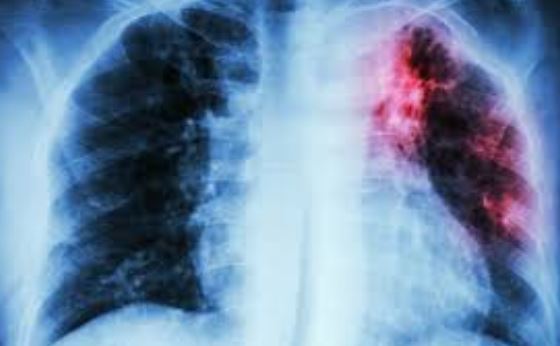

TB

In 2024, thirty-five persons died from tuberculosis (TB)-related complications across Nasarawa State.

He revealed that the state recorded 8,190 TB cases in 2024, with 21 per cent of the patients co-infected with HIV.

“The TB prevalence rate in 2024 was higher than in 2023, when we recorded 7,275 cases, with 18 per cent of them co-infected with HIV,”